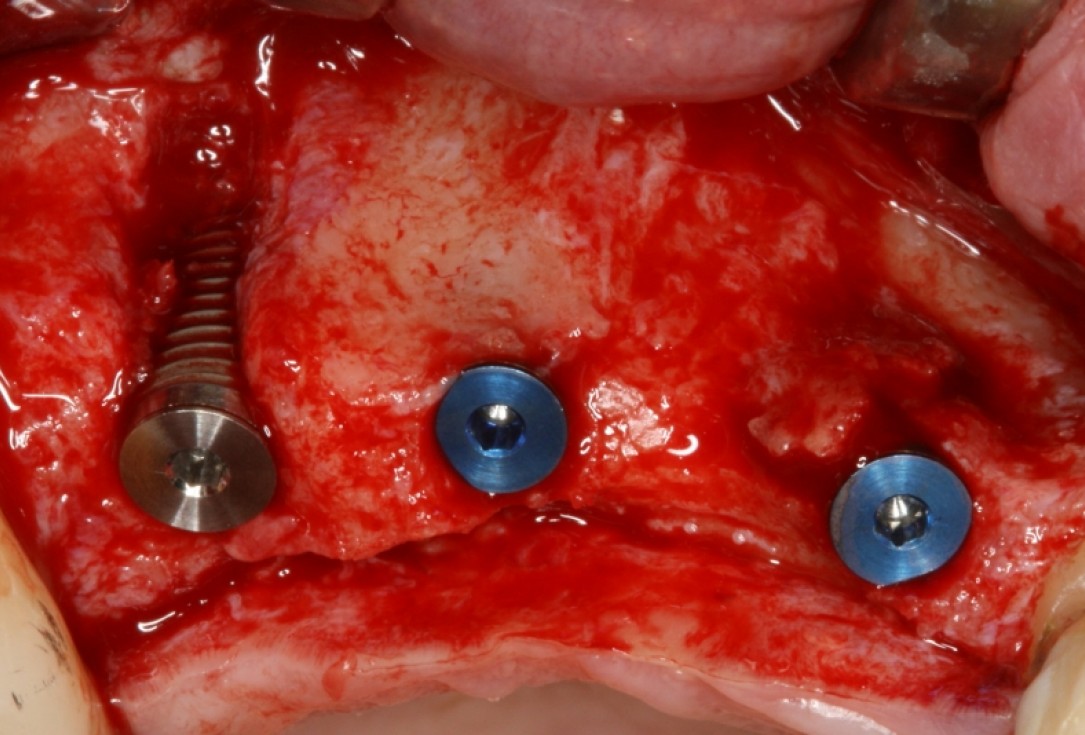

botiss cerabone® & Jason® membrane for GBR - Clinical case by Dr. S. Kovalevsky

Implant insertion in atrophic alveolar ridge